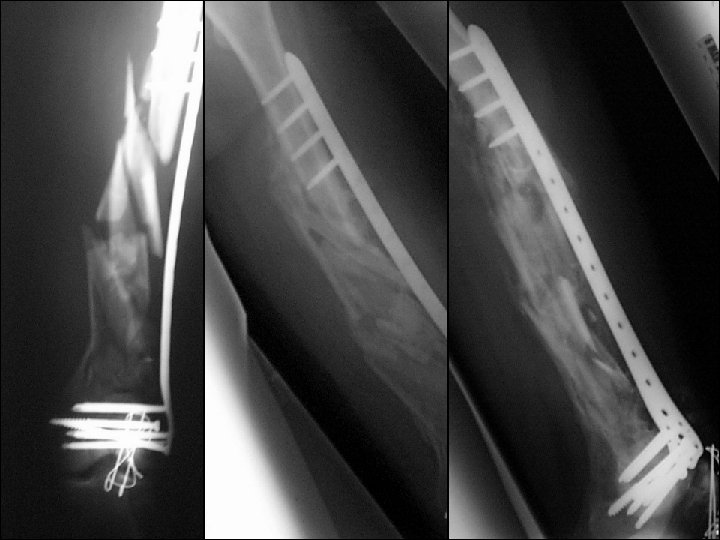

28 -year-old male, motor vehicle accident, subtrochanteric femoral fracture

Reduction? 1. Open direct reduction 2. Closed indirect reduction 3. Mini-open reduction

How would you achieve an indirect reduction? 1. Fracture table 2. Regular radiolucent table 3. Femoral distractor/external fixator 4. Implant as a reduction aid